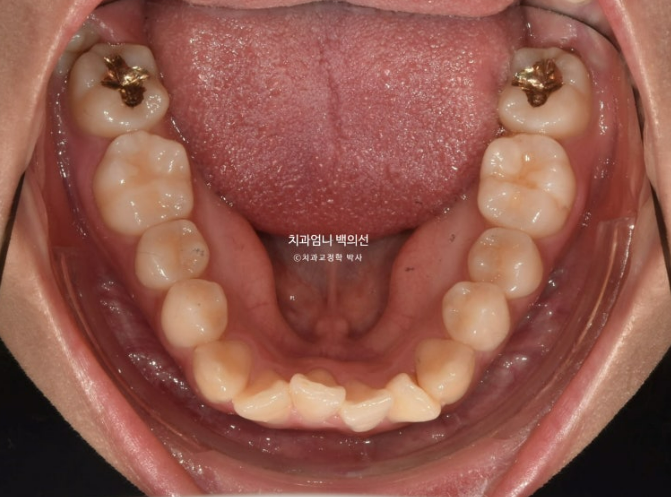

2023년 12월 앞니 부분교정을 원해서 내원한 분 입니다.

앞니 두 개가 크기도 하고 내려와 있습니다.

파란 화살표에 작은어금니 덧니도 보입니다.

아래 앞니가 많이 삐뚤 합니다.

어금니 교합이 그리 좋은 편은 아니었지만 환자분은 씹는데 불편함을 못 느끼는 상태였고 앞니 배열만 원하셨습니다.